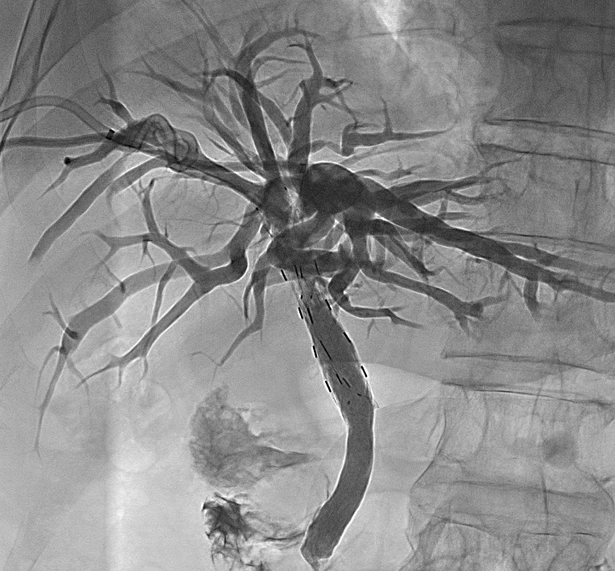

协同效应

支架提供即时的胆道再通,放射性粒子则通过持续照射延缓肿瘤向支架腔内生长,两者协同实现更持久的治疗效果。。

粒子支架长期保障胆管通畅

粒子能量在支架内局部释放,引流的同时,使支架再通

95%

支架再通率

由于造成恶性梗阻的肿瘤会持续生长,导致普通支架或引流管短期内再堵塞。普通支架植入+粒子导管能抑制肿瘤生长,从而显著延长胆道的通畅时间;或者不植入支架,单独使用粒子导管也能起到抑制肿瘤并保持胆管长期通畅。